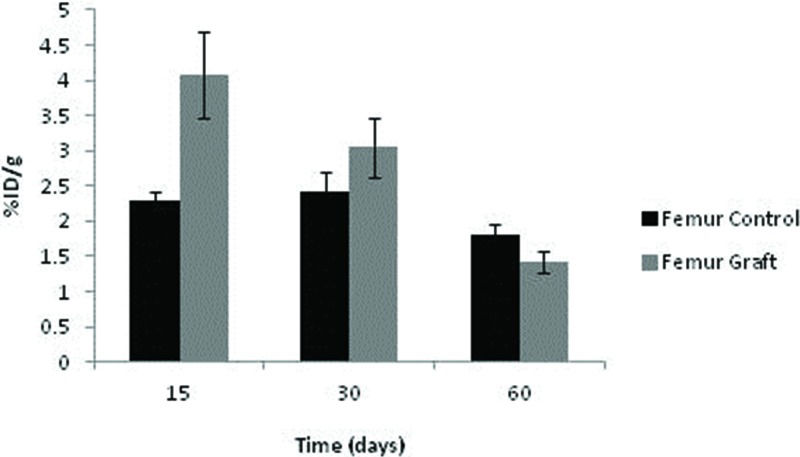

The uptake of 99mTc-HYNIC-E-c(RGDfK)2 by the control femurs displayed some fluctuations depending on the time point, although no significant difference was noted. Among the grafts, the uptake was highest after 15 days (p=0.016) and subsequently diminished at 30 and 60 days (p=0.040 and p=0.043, respectively). Consequently, graft uptake exceeded that of controls under all circumstances (Figure 6).

No significant differences in 99mTc-MDP were detected over time among the syngeneic implants or control femurs, although a tendency toward graft reduction at 30 and 60 days was evident. As expected, the control uptake was substantially higher than in the ischemic grafts. It should be emphasized that the avascular graft values were not negligible, indicating sustained viability and metabolic activity, as documented with 99mTc-HYNIC-E-c(RGDfK)2 (Figure 7).